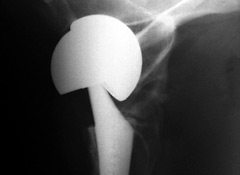

Case in point: the DePuy ASR XL metal-on-metal hip replacement, which was implanted in 93,000 people worldwide before it was finally taken off the market in 2010 because it was failing at an unacceptably high rate.